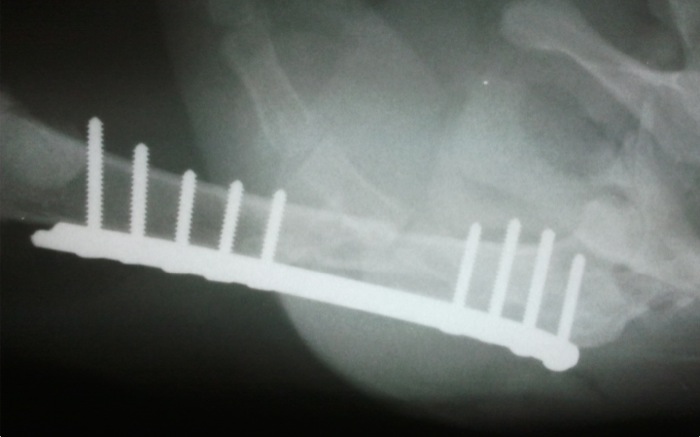

Se colocan, con abordajes que se alienan desde la piel el fémur y el ileon, las placas correspondientes. El fémur presenta una amplia zona diafisaria media solo con la cortical posterior intacta lo que impide la colocación de tornillos en mas de un tercio de la longitud de la placa.

Aún así se consigue una estabilidad completa y fuerte del hueso dañado.